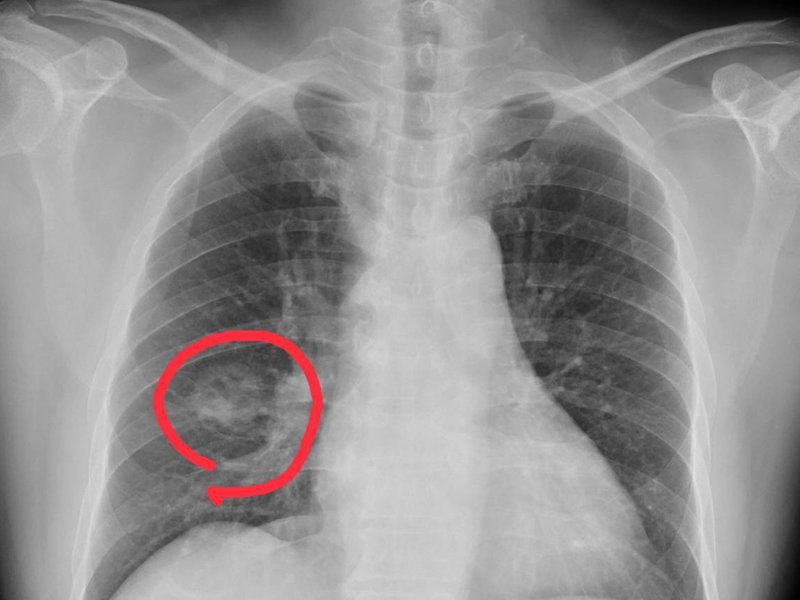

3. 雙手雙手腳麻痺

當肺部有惡性腫瘤時,由於癌細胞對肺組織的侵襲,會影響肺部的呼吸功能,導致體內氣體交換異常,導致患者全身缺氧,而人體的手腳屬於末端,這種現象尤其明顯,因此會出現手腳麻痺的症狀。